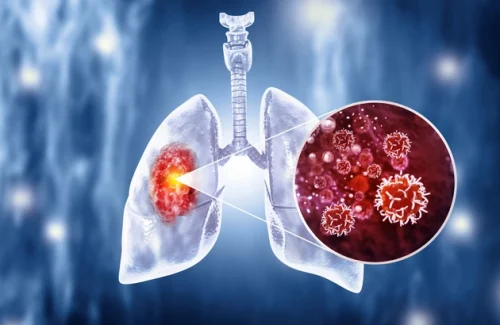

Akciğer kanseri, akciğerlerde kontrolsüz hücre büyümesi sonucu oluşan bir tür kanserdir. Genellikle sigara içmek gibi risk faktörleri ile ilişkilidir, ancak sigara içmeyenlerde de görülebilir. Erken teşhis edilmediğinde, akciğer kanseri ilerleyebilir ve tedavi edilmesi zor olabilir. Bu nedenle, belirtileri tanımak ve risk faktörlerini azaltmak önemlidir.

Akciğer kanseri teşhisi genellikle görüntüleme testleri (örneğin, bilgisayarlı tomografi veya BT taraması) ve biyopsi ile konulur. Tedavi seçenekleri tümörün tipine, evresine ve hastanın genel sağlık durumuna bağlı olarak değişir. Tedavi seçenekleri arasında cerrahi müdahale, kemoterapi, radyoterapi ve hedefe yönelik ilaç tedavisi bulunmaktadır. Erken teşhis, tedavi seçeneklerini ve hastalıkla başa çıkma şansını artırabilir.